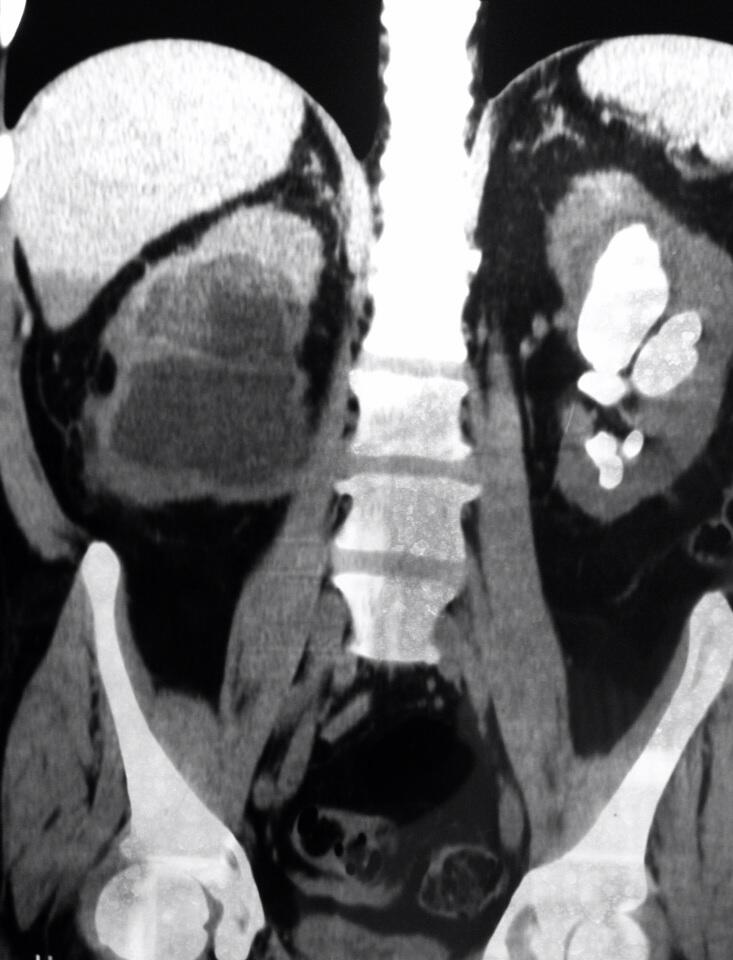

Corresponden al 10-15% de las litiasis siendo su prevalencia mayor en las mujeres que en los varones. Adoptan un color apagado o marrón claro, son infecciosas y a veces son tan grandes que forman los cálculos coraliformes que son unas grandes piedras que se forman dentro de las cavidades renales. Si no son tratadas a tiempo pueden producir pielonefritis (infección del riñón) y un importante deterioro de la función renal. El problema es que muchas veces estas piedras no dan síntomas en sus fases iniciales y se acaban descubriendo cuando tienen un tamaño considerable, muchas veces en el contexto de un estudio por infecciones urinarias de repetición.